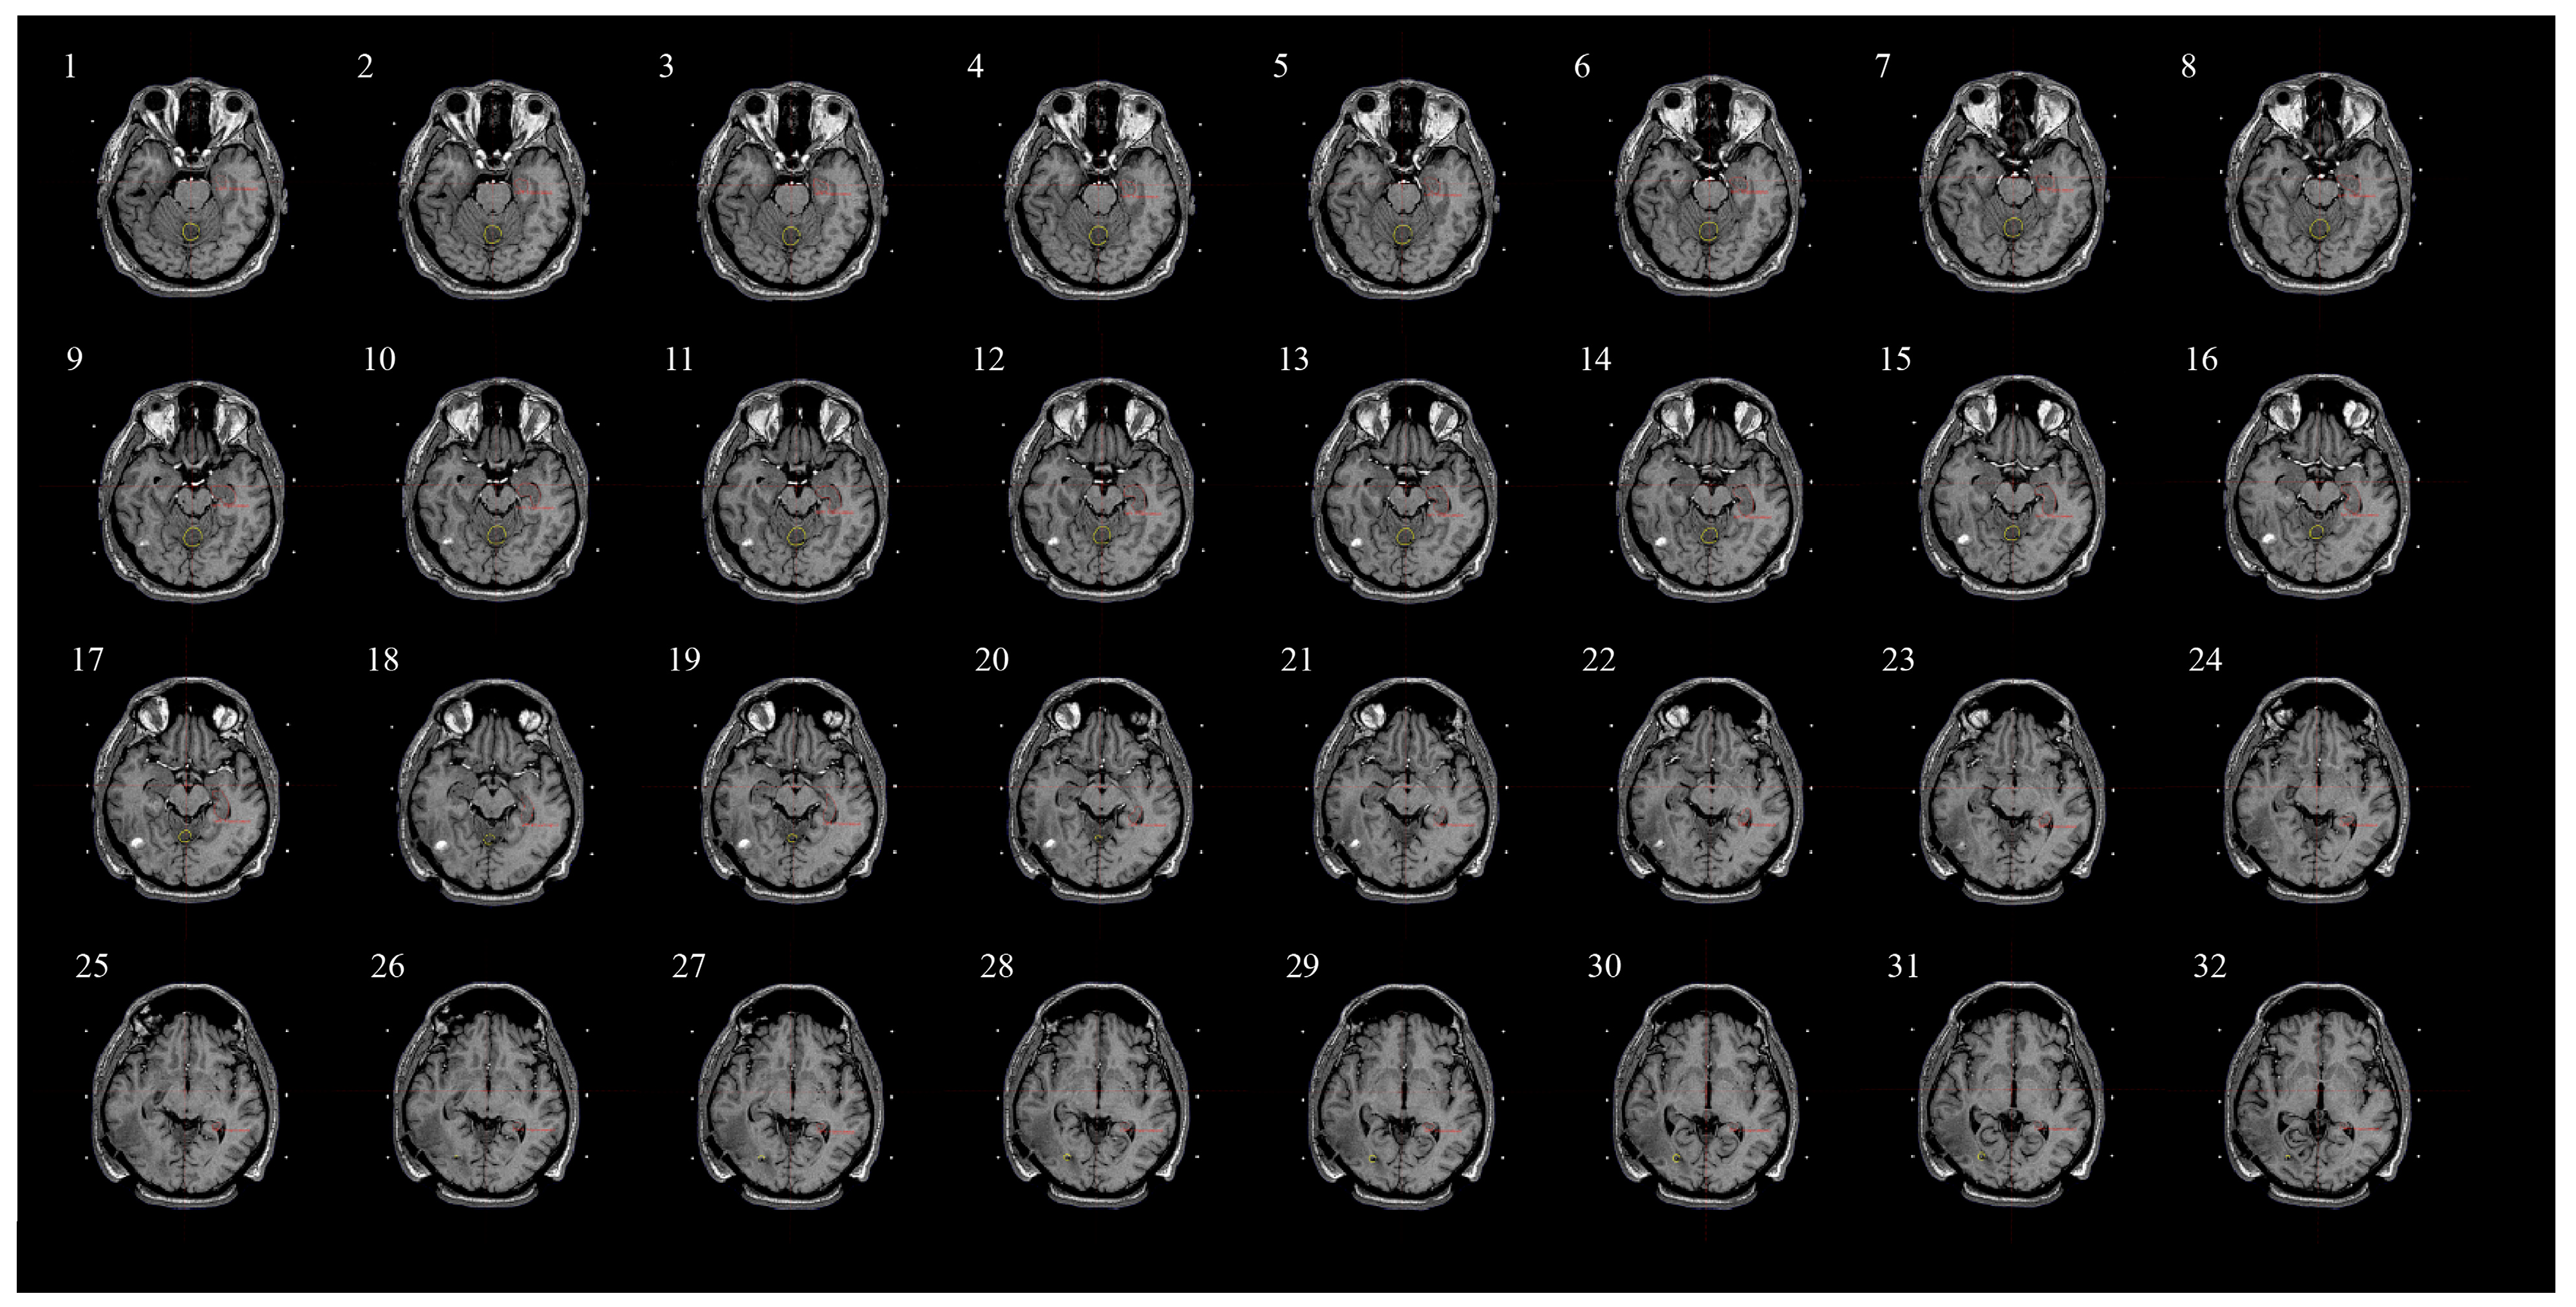

2.5. Assessing Radiation Dose to Hippocampi and Contouring Process